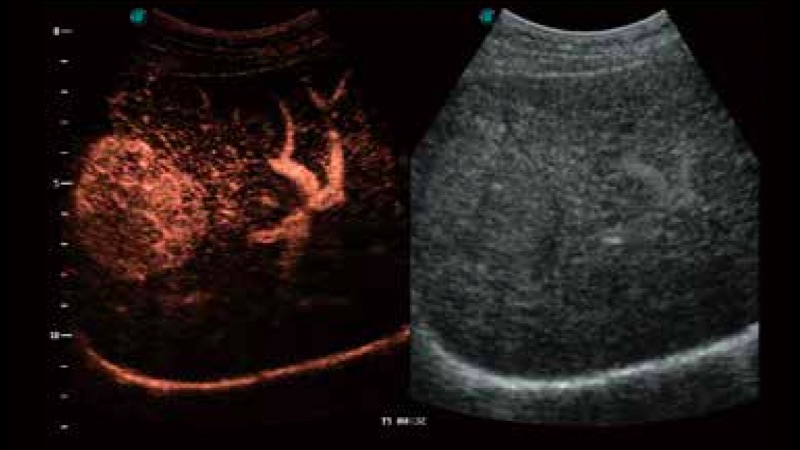

造影成像

造影成像功能和定量分析工具包使医生能够更好的评估血流灌注情况。独特的动态声压控技术有效控制造影剂的声压,保证更长的造影剂持续时间,更好的观察病变灌注的延迟相位。

临床图像